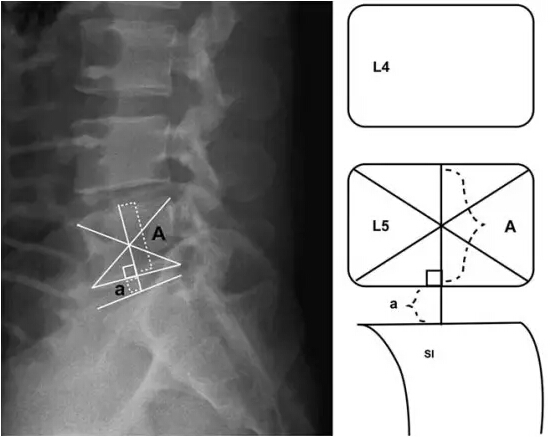

测量椎间盘高度 = a

测量髂嵴高度指数(IHI)= a/A